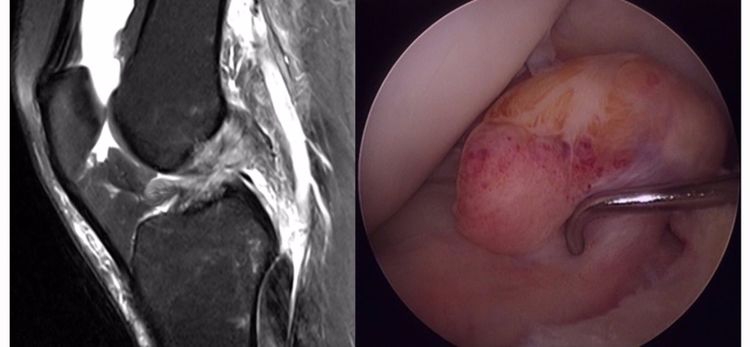

ACL损伤的直接征象:指ACL本身的形态和信号异常。一旦有了明确的直接征象就可以确定ACL损伤。

1.不连续:有韧带的低信号,但中断不连续。一般见于新鲜损伤。

2.方向异常(ACL 下垂征):有较完整的韧带低信号,但方向异常,呈下垂状。一般见于股骨附着部的陈旧损伤,损伤的ACL下垂并粘附在PCL上。

3.ACL 消失:髁间窝空虚,无韧带信号。见于较久的损伤,损伤的ACL撕裂较重呈马尾状,无滑膜包裹,逐渐被关节内的酶腐蚀而消失。

4.撕脱骨折:一般为ACL胫骨附着部的撕脱,韧带完整,信号多正常。

5.假瘤:韧带损伤后断端较整齐,残端组织增生并被滑膜包裹呈"瘤状",如果突出于前方为"独眼征",多见于韧带股骨附着部撕裂及部分撕裂。

6.扭曲和空虚:髁间窝内似隐隐约约有低信号,边缘明显,中央空虚;或者中央有低信号,但扭曲如麻花状。多为陈旧损伤,仅存ACL的滑膜,里面可有少量的韧带纤维,粘附在后方,随着膝关节的长时间屈伸逐渐呈扭曲状。